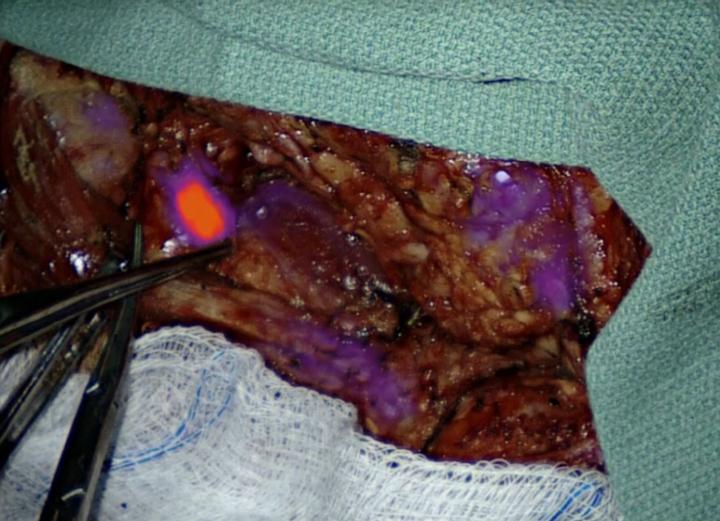

PHILADELPHIA - Surgeons at Penn Medicine are using a fluorescent dye that makes cancerous cells glow in hopes of identifying suspicious lymph nodes during head and neck cancer procedures. Led by Jason G. Newman, MD, FACS, an associate professor of Otorhinolaryngology in the Perelman School of Medicine at the University of Pennsylvania, the study is the first in the world to look at the effectiveness of intraoperative molecular imaging (IMI) of lymph nodes in patients with head and neck cancer. Because the tumors glow, surgeons get real-time guidance to help them take out as much cancer as possible and leave non-diseased tissue alone.

"By using a dye that makes cancerous cells glow, we get real time information about which lymph nodes are potentially dangerous and which ones we can leave alone," Newman said. "That not only helps us remove more cancer from our patients during surgery, it also improves our ability to spare healthy tissue."

It's a concept already in practice for other disease sites in the Abramson Cancer Center's Center for Precision Surgery, led by Sunil Singhal, MD, the William Maul Measey Associate Professor in Surgical Research. Singhal's team has adopted the approach in lung cancer and brain cancer, and now Newman and his team are the first to specifically use IMI to look at lymph nodes. They're using a contrast agent known as indocyanine green (ICG) - a fluorescent dye that was approved decades ago by the U.S. Food and Drug Administration for use in tracking blood flow.

"We know that tumors hold onto this dye longer than most other tissues, so if it is administered to a patient several hours before surgery, the tumors will still glow long after it has disappeared from the rest of the body," Newman said.